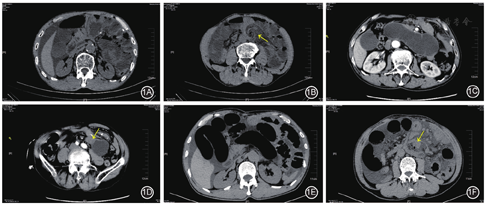

所有患者均为急诊入院,术前CT示所有患者均表现为小肠扩张积液,其他常见影像学表现包括漩涡征、靶征、肠系膜回缩或充血水肿、腹盆腔积液等。典型病例CT影像特征见图1。全组患者均伴腹盆腔积液,中位积液量750(100~3 000)ml。